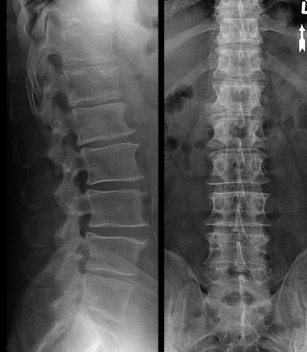

Scoliosis

Abnormal or exaggerated lateral curvature of the spine

Most common in 10-14 y/o, more in females

Severe scoliosis cases may complicate ____ function and require surgery.

Cardiac and respiratory

Treatment for scoliosis includes ____ which can be adjusted as the child grows.

Expandable, permanent correction rods